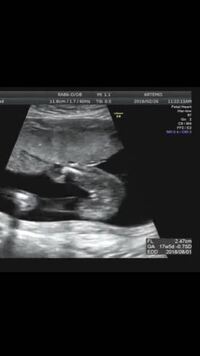

性別 女の子 赤ちゃん エコー- 妊娠14週の性別判断について。 待望の第二子、妊娠中です。 写真は、先日13週目の検診でいただいたエコー動画の一部です。 これはもしや男の子かな?と思えるようなちょこんと出てなんて漠然と思っていたので、19週頃に言われた性別から変わった方がいたり、周りにいたという方の話をお聞かせいただきたく^_^ こないだの検診19w3dの時に 性別が男の子だと言われました🐘

男の子の性別判定はいつから可能? 男の子の性別判定はいつから可能なのでしょうか? 男の子の性別判定は比較的早く、早くて15週・16週ごろからシンボルが見えてくる ようです! 私 多分これは男の子だね~ と先生に言われ、性別が判明したものの確定とはならず。, 妊娠19週6日の検診で、予想通り男の子と確定しました!, !, !, 妊娠初期 (11週、12週、13週)ベ